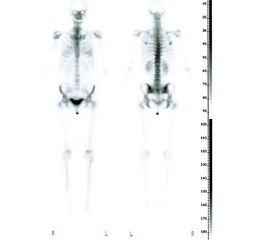

Grundlage der Skelettszintigraphie ist die Verwendung von osteotropen Radiopharmaka, die nach intravenöser Applikation zur Beurteilung der locoregionären Durchblutung (Hyperperfusion) und zur Abklärung des Knochenstoffwechsels verwendet werden. Indikationen zur Skelettszintigraphie sind entzündliche und tumoröse Skeletterkrankungen, Abklärungen von Prothesenlockerungen und in individuellen Einzelfällen auch zur Detektion occulter Frakturen (z.B. bei Kindesmißhandlung) (Schümichen C. 2006), (Schümichen C., et al. 2006). Dabei wird je nach Fragestellung ein statisches und/oder dynamisches Untersuchungsprotokoll durchgeführt, z.B. eine statische Skelettszintigraphie zur Verlaufsbeurteilung von bekannten ossären Metatasen oder eine 3-Phasen-Skelett-Szintigraphie bei Verdacht auf eine Prothesenlockerung. Die zusätzlich zur Szintigraphie angewendete SPECT-Technik (rotierende Gamma-Kamera) erlaubt eine höhere Ortsauflösung sowie eine artefaktfreie Darstellung etwaiger knöcherner oder anderer Läsionen. Im Vergleich zur CT ist die Strahlenbelastung gering (Schümichen C. 2006).

In den letzten Jahren sind die Indikationen zur „reinen“ Skelettszintigraphie deutlich zurückgegangen. Ursache sind die kombinierten nuklearmedizinisch/radiologischen Untersuchungsverfahren SPECT-CT und PET-CT, die gegenüber der Szintigraphie und auch der Computertomographie eine deutlich höhere Sensitivität und Spezifität aufweisen 1. Diese Verfahren erlauben gleichzeitig eine funktionelle und morphologische Bildgebung. Auch die MRT stellt zur Skelettszintigraphie in den meisten Fällen eine sinnvolle Alternative dar (Haug A et al. 2006).